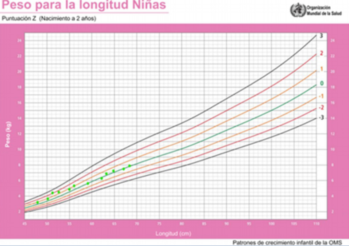

El crecimiento en peso, longitud y perímetro craneano según la edad se muestran en las (Figura 1), (Figura 2) y (Figura 3). En la (Figura 4) se muestra la evolución del peso de acuerdo a la longitud.

Figura 4: Gráfica longitud para el peso. Los puntos verdes indican los valores para esta paciente de acuerdo a la edad.